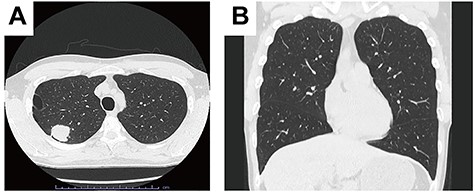

This is the case of a 38-year-old man with cStage IB adenocarcinoma. Computed tomography showed a 33-mm mass in the right upper lobe (Fig. 1A), and no interlobar fissure between the right upper and middle lobes (ho. 1B).

Computed tomography showed a 33 mm mass in the right upper lobe. A. No interlobar fissure between the right upper lobe and middle lobe